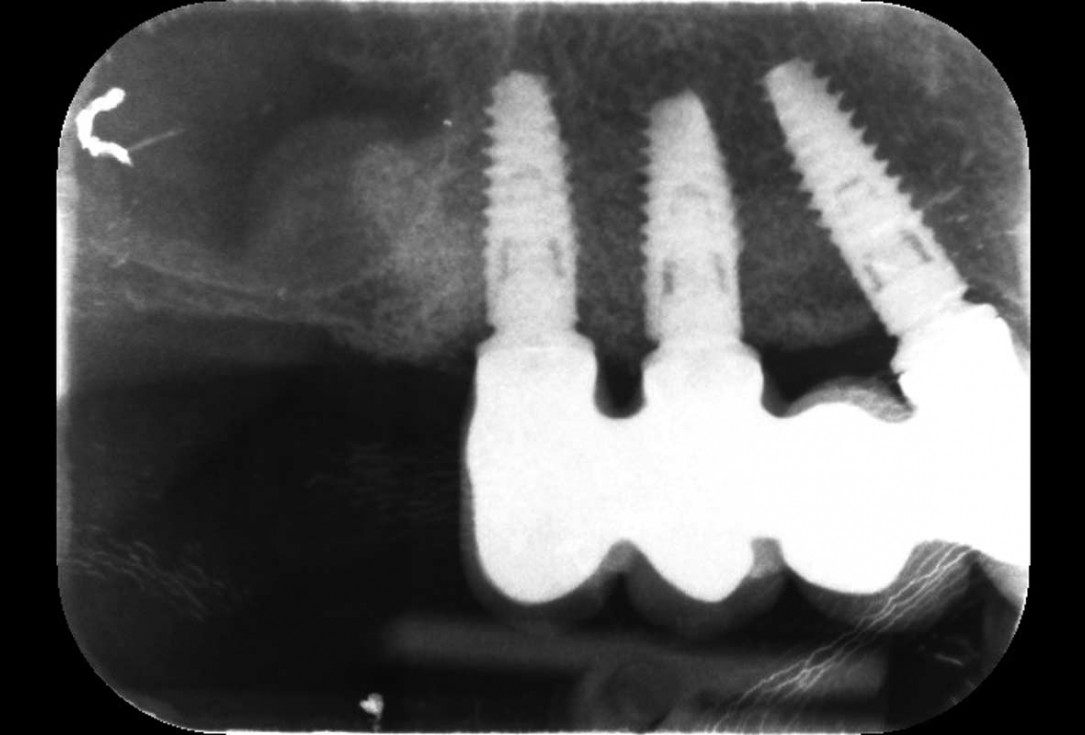

12/12 - Radiographic control with final prosthetic restorationHorizontal ridge augmentation with permamem®, cerabone® and autologous bone chips - Dr. S. Pelekanos

Three implants placed in a narrow posterior mandible